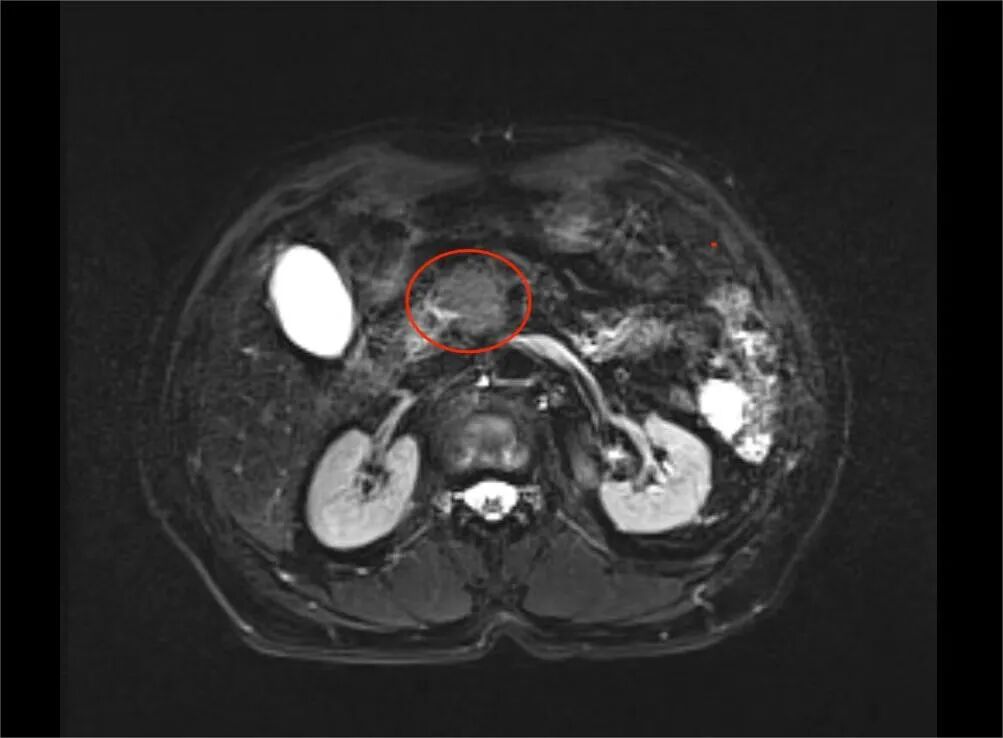

2023年12月,年过七旬的屠先生,因为上腹隐痛、胃口不好,来到医院检查,腹部B超和腹部增强磁共振都提示胰腺头部肿块,高度怀疑胰腺癌。胰腺癌俗称癌王,恶性程度极高,预后不佳,屠先生一家大吃一惊,一刻不敢耽误,立即赶到无锡人民医院普外科就诊。

结合上述指标,屠先生胰腺头部肿块需考虑自身免疫性胰腺炎的可能性,口服激素治疗后2024年03月复查,胰腺CT提示胰腺肿块明显缩小,患者的诊断得以明确。